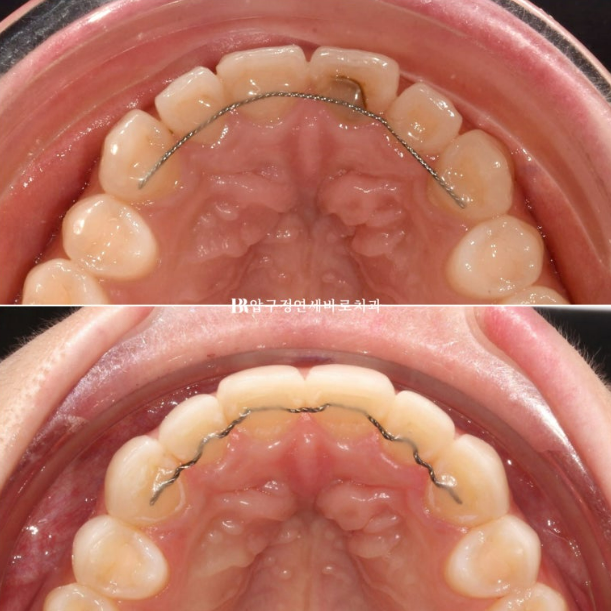

Let’s compare occlusal surface photos so you can get a sense of how thin Gelami is.

The image above is the initial visit, and the one below shows all 8 teeth fitted with no-prep laminates without any removal.

The fact that there is no noticeable difference in thickness shows how thin Gelami is.

At the thinnest point, it can be reproduced down to 0.1 mm.